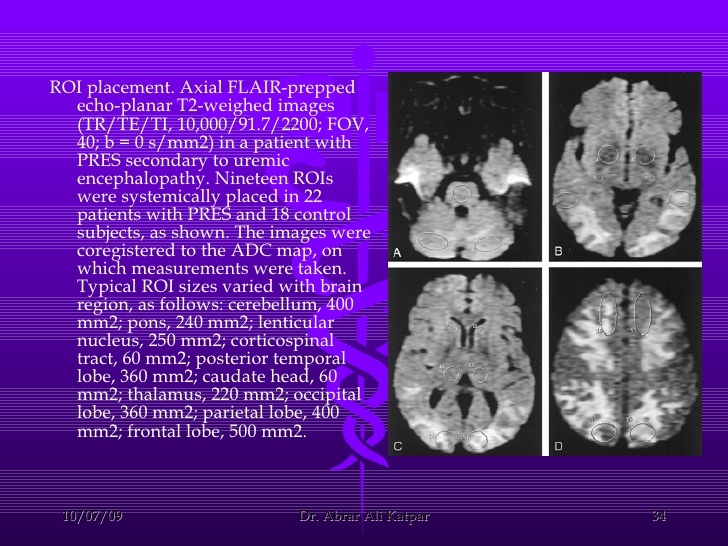

尿毒症性脑病